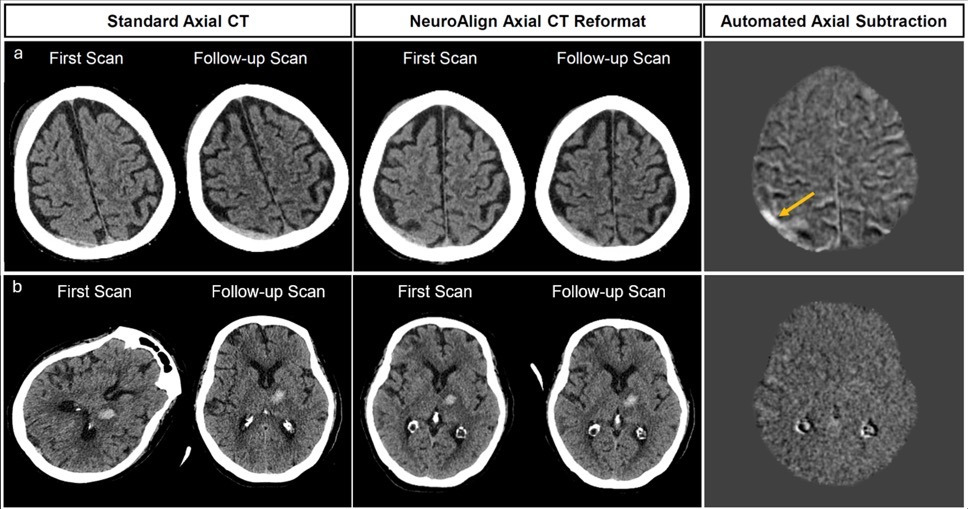

First panel original scans, second panel NeuroAlign images and third panel subtraction images (new minus old) showing enlarging SDH (upper image) and stable parenchymal hemorrhage (lower image).